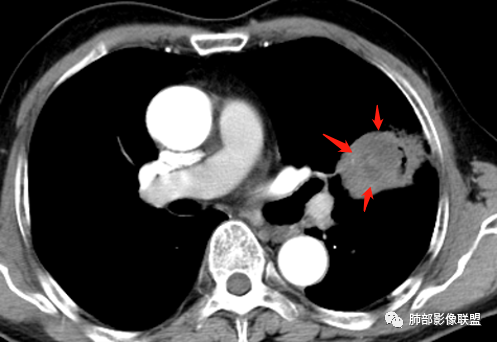

中远端堵塞,堵塞端圆钝

炎性? 肺炎型肺癌待排

血管受侵了吧

空洞内侧软组织肿块,比较支持恶性吧

这个空洞的性质很重要,对最后诊断结果影响大,如果中间没有曲菌球,那就是偏心空洞,指向恶性,如果是曲菌球引起的新月形改变,那就不一定。至于到底是曲菌球还是偏心空洞,需要仔细看看强化情况。

不均匀性强化,远端坏死比较明显

如果强化明确,那就可以排除曲菌球。